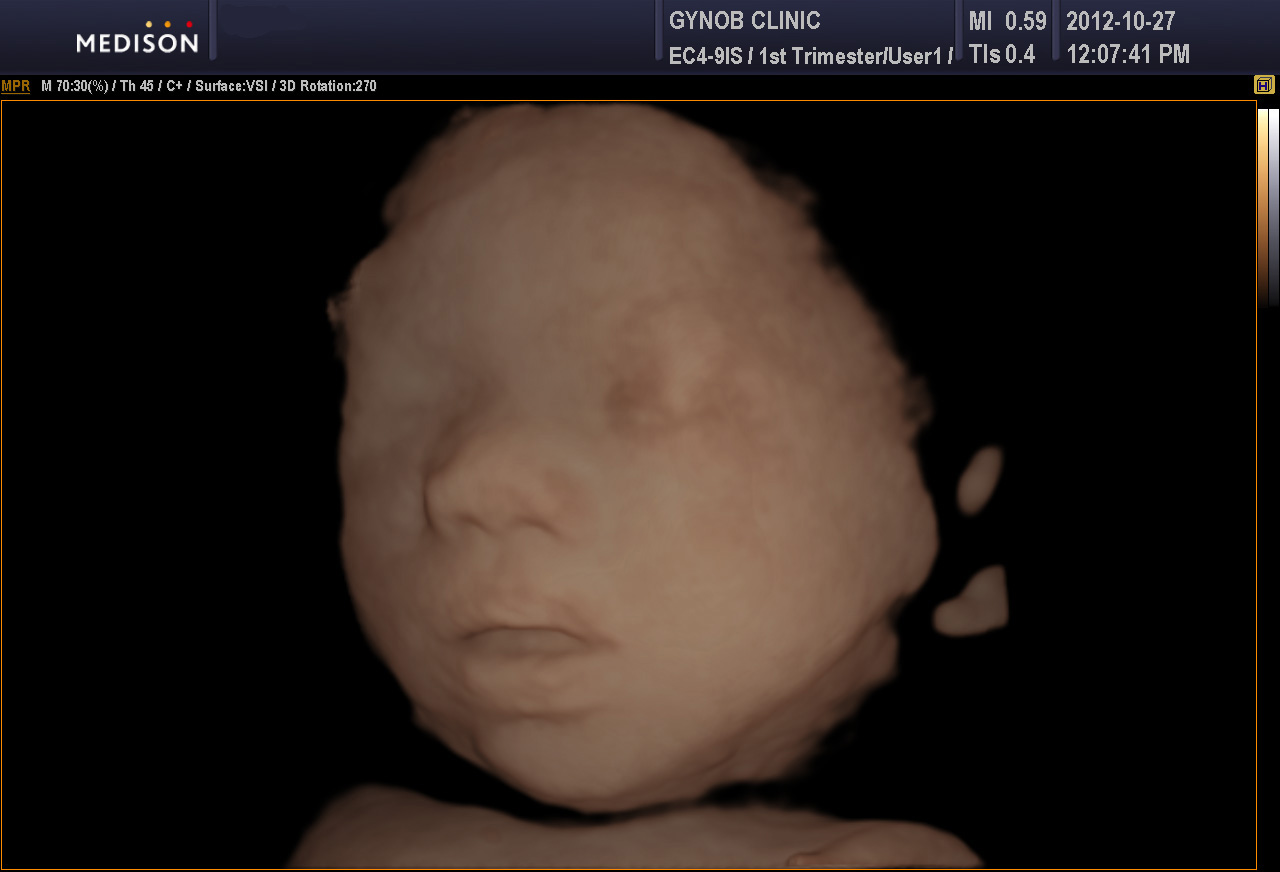

위 사진은 일반 2D 이미지 사진이고 아래는 입체 초음파 사진입니다.

구순열이 있을 경우 연속된 선이 끊어진 것으로 나타납니다.

구순열 태아의 초음파 사진을 어딘가 보관해 두었던 것 같은데 찾지 못하여 정상 사진을 올려 두는 점 양해 부탁드립니다.